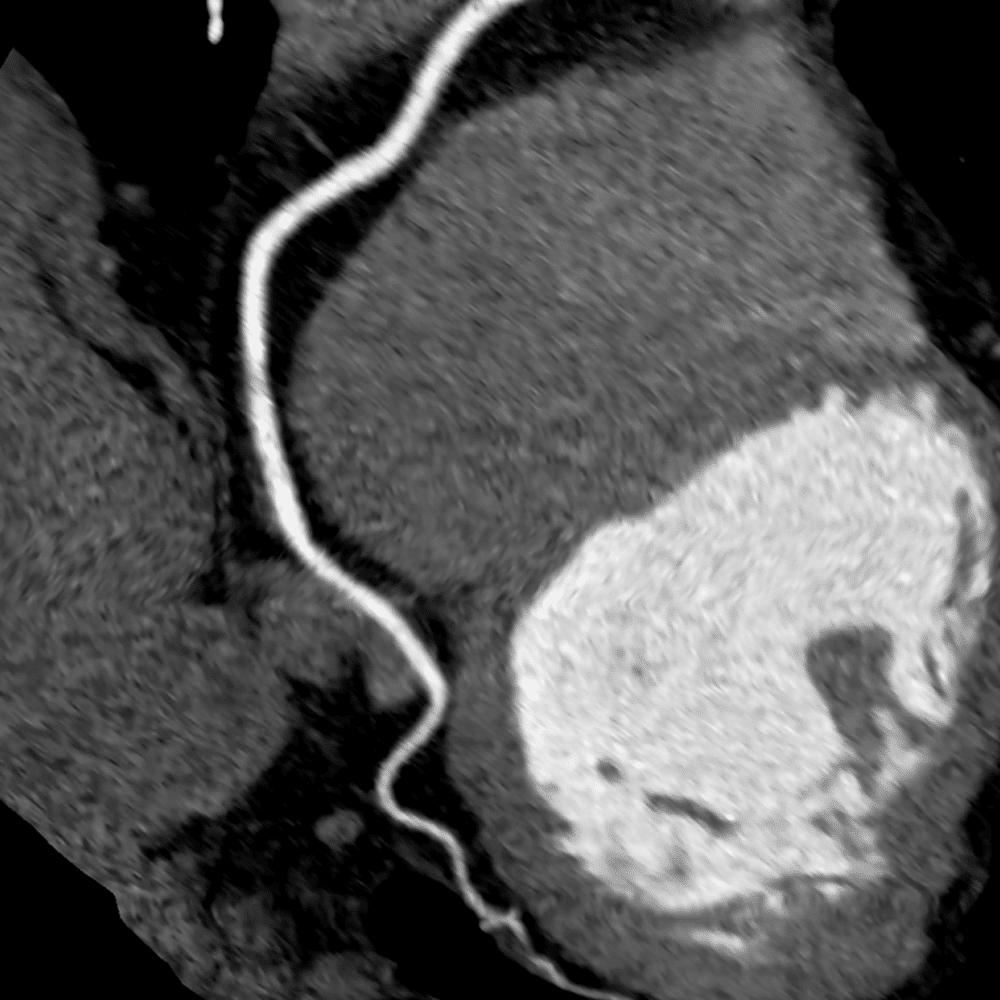

Cardiac CT Angiography (Cardiac CTA) and Calcium Scoring is a sophisticated imaging technique that uses CT technology to visualize the coronary arteries in great detail; especially for detecting narrowed or blocked coronary arteries from atherosclerotic plaque: hallmarks of coronary artery disease (CAD). Heart disease is the #1 cause of morbidity & mortality in the world. This exam includes a calcium scoring test as well (excellent value). This is a private, self-pay service and is not covered by OHIP.

CT Angiography with Contrast

Uses iodinated contrast to visualize blood flow within the coronary arteries

This Cardiac CT exam helps assess atherosclerotic plaque that causes narrowing of the coronary arteries which leads to heart attacks or myocardial infarct. In addition, the study provides a calcium score which measures calcification of the coronary arteries. This is an excellent test to check for heart disease. typically used in coordination with your healthcare provider and does not replace emergency care or other heart tests they may recommend.